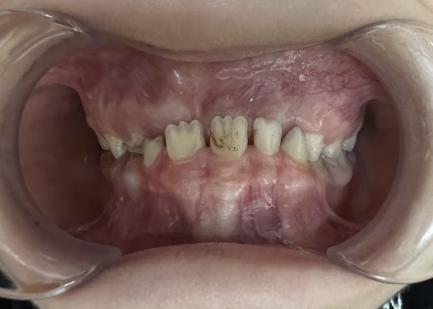

案例二:

治疗前

治疗后